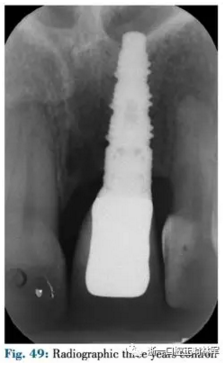

4月后在最終修復前使用臨時冠擠壓齦乳頭(圖48,49)。